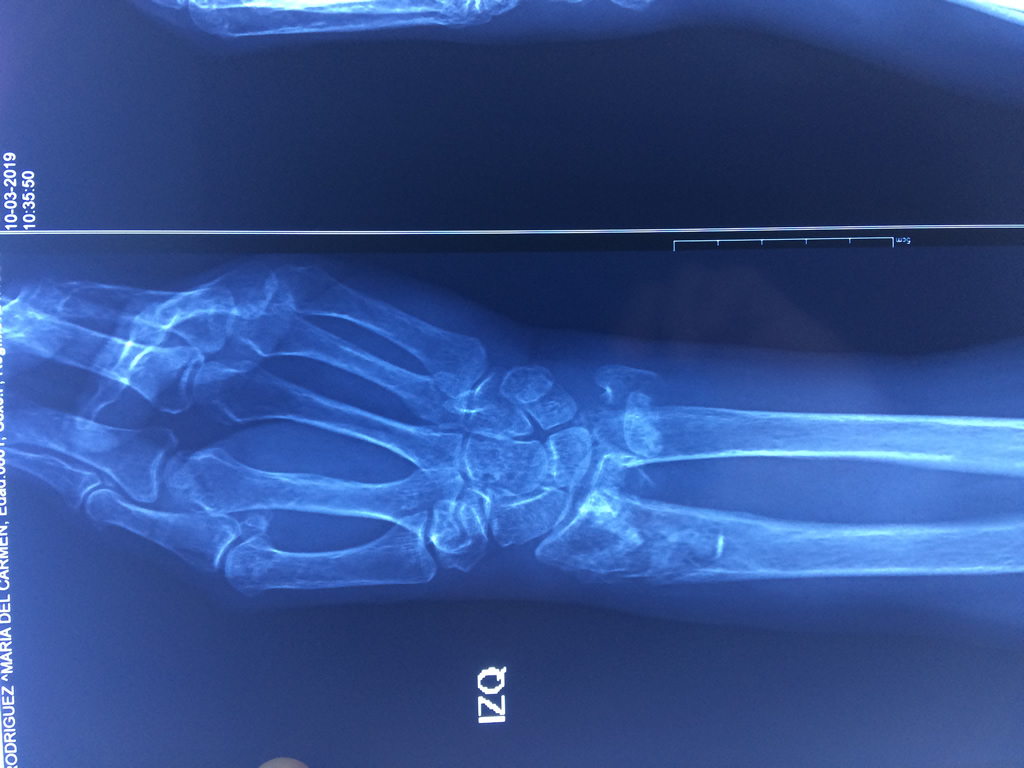

Cirugías de Muñecas

Los procedimientos más comunes en cirugía de la mano son aquellos destinados a reparar traumatismos, incluyendo lesiones de tendones, nervios, vasos sanguíneos, y articulaciones; huesos fracturados; y quemaduras, cortes, y otros daños de la piel.